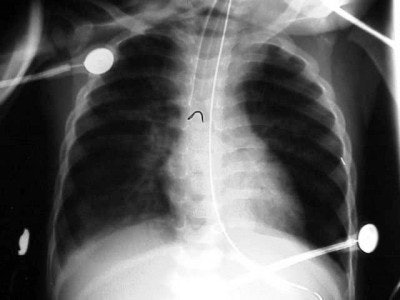

In figure 5 we have the chest x-ray of a six-month-old infant with cough, fever, and shortness of breath (SOB). Nine pairs of ribs are visible, the arms are raised above the child’s head, and there is no evidence of rotation. Pathologically, he has right upper lobe aspiration pneumonia (arrow). The darker area in the left lung base was diagnosed as a pneumothorax, cardiomegaly; something is displacing the ET tube to the right. A chest CT was recommended for further evaluation.